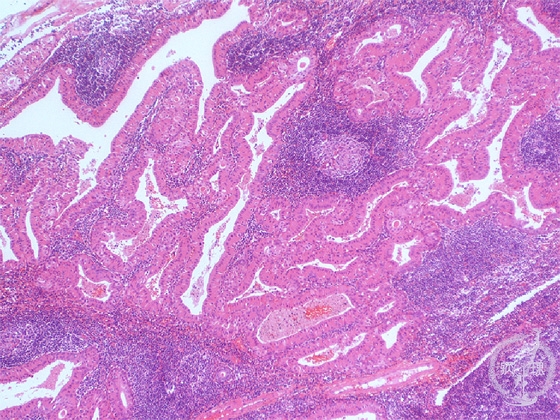

- 7.Oral, Salivary gland

- (7)Salivary gland tumor(★Warthin tumor)

Microscopic finding (HE stain, low-power view):The eosinophilic tumor cells lining the cystic spaces form papillary processes which protrude into the cysts. The stroma includes lymphoid tissue with follicle formation (*).